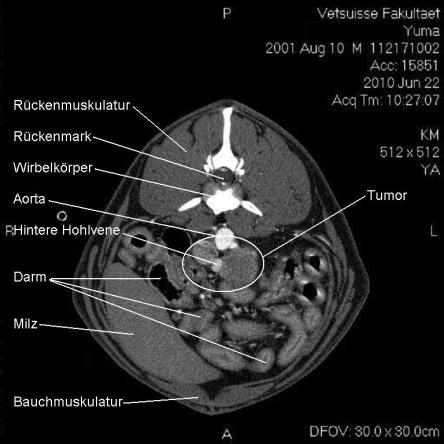

Die Computertomographie (CT) liefert mittels eines röntgenähnlichen Verfahrens ein dreidimensionales Bild des untersuchten Körperteils. Da das untersuchte Tier vollständig ruhig liegen muss, wird Yuma zur Untersuchung narkotisiert.

Im CT wird ersichtlich, dass sich der Tumor, welcher von der linken Nebenniere ausgeht, schon sehr weit in das Gefässystem von Yuma vorgearbeitet hat. Krebsausläufer finden sich wie erwartet in der Hohlvene, aber auch in der Nierenvene sowie in einer weiteren grossen Vene. Der Geschwulst ist somit inoperabel.